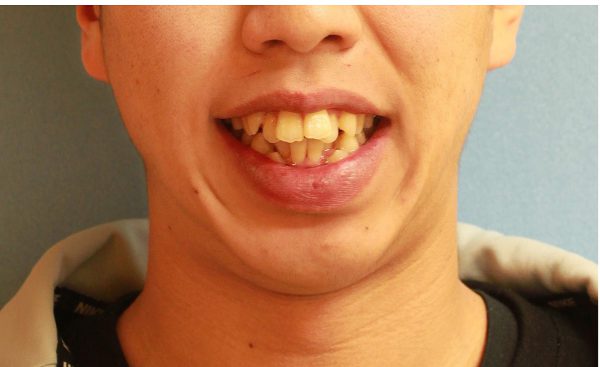

20歳 男性「 八重歯 出っ歯 を治したい」( 叢生、上顎前突症)

20歳の 男性です

「 ガチャガチャの歯ならびと ” 出っ歯” を治したい」との事で来院されました。

上下の歯が重なり合っています。

特に下の歯ならびの重なりは激しいです。

ガチャガチャが気になりますが、上の前歯が前に飛び出ているため、”出っ歯”の状態となっています。

横から診ると出っ歯の程度としても激しいですね。

重度の叢生を伴う 上顎前突症 です。

ガチャガチャの激しい歯ならびと

出っ歯のため口もとの雰囲気が良くありません。

(お顔の写真の使用にはご本人の承諾を頂いています)

人と会うときに ガチャガチャの歯ならびが社会人として恥ずかしく、

なんとか改善できないかと悩んでいたとの事でした。

治療を決断され(抜歯には抵抗があったそうです)

上下左右の抜歯を行い、ガチャガチャの歯ならびを整えました。

前歯もできる限り後方へ移動させ、口もとを下げました。

2018年の1月15日にスタートして 2019年の8月27日に 終 了 しました。

治療期間は 20か月 でした

激しいガチャガチャは改善され、八重歯の痕跡もありません。

良く動きました (#^.^#)

上の前歯もしっかりと下がり ”出っ歯” 感も解消されました。

口もとの 印象が 大きく変わり 人と接する時にも 自信を持てるとの事でした。

素敵な笑顔になりました! (#^.^#)

20歳 男性 著しい叢生を伴う上顎前突症 治療期間 20か月 唇側矯正装置(ホワイトワイヤー)と内側からの固定装置を使用した上下顎小臼歯抜歯治療 参考治療費 約67万円 (精密検査から終了まで) 矯正治療に伴う副作用の歯肉退縮、知覚過敏、歯根吸収などは認められませんでした。